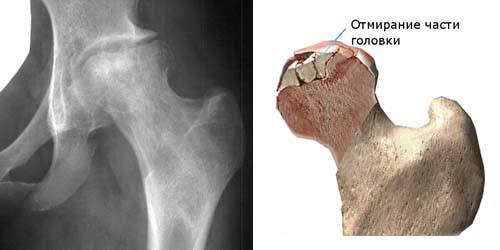

Кости нашего скелета состоят из костной ткани, которая, как и большинство других тканей организма состоит из живых клеток и содержит кровеносные сосуды (артерии, капилляры и вены). При нарушении местного кровоснабжения возможно развитие омертвения (некроза) ткани или органа, что может приводить к серьезным проблемам. Нарушение кровоснабжения возникает при закупорке (тромбозе или эмболии) артерий, которые кровоснабжают данную область. Особенно часто некроз тканей возникает в областях, которые кровоснабжаются из бассейна единственной артерии. К таким «проблемным» зонам относится головка бедренной кости. При нарушении кровоснабжения этой области возникает заболевание, которое называется асептическим некрозом (АН) головки бедренной кости.

Анатомические аспекты:

Тазобедренный сустав является самым большим шарообразным суставом нашего тела. Он формируется из глубокой суставной впадинытазовой кости (ацетабулярная впадина) и головки бедренной кости. Тазобедренный сустав окружен мощными мышцами (ягодичными и мышцами передней группы бедра). Ацетабулярная впадина и головка бедренной кости покрыты суставным (гиалиновым) хрящем. Суставной хрящ имеет очень гладкую скользкую поверхность, а его толщина в тазобедренном суставе достигает 0,5-0,6 Функция суставного хряща состоит в снижении трения при движениях в суставе и амортизации ударных нагрузок. Головка бедренной кости кровоснабжается единственной артерией, которая проходит через шейку бедренной кости. В связи с отсутствием коллатерального кровообращения при прекращении тока крови по этой артерии нарушается кровоснабжение головки бедренной кости. В результате развивается некроз (омертвение) головки бедра. Некроз приводит к ухудшению механических свойств костной ткани. Кость не является «застывшей» структурой. В костной ткани постоянно происходит разрушение костных балок и одновременно протекают регенеративные процессы. Прекращение восстановительных процессов вследствие недостатка кислорода и питательных веществ ведет к быстрому ухудшению механических свойств костной ткани. В результате под воздействием механических нагрузок происходит коллабирование (спадение) некротизированного участка кости. При развитии АН форма головка бедренной кости изменяется: происходит ее уплощение в области максимального воздействия силы тяжести. В результате нарушается конгруэнтность (сочленяемость) суставных поверхностей в тазобедренном суставе, что приводит к увеличению внутренней нагрузки при работе сустава и быстрому изнашиванию суставного хряща. Исходом АН является развитие остеоартроза – дегенеративного заболевания сустава, сопровождающегося болью и нарушением его функции.